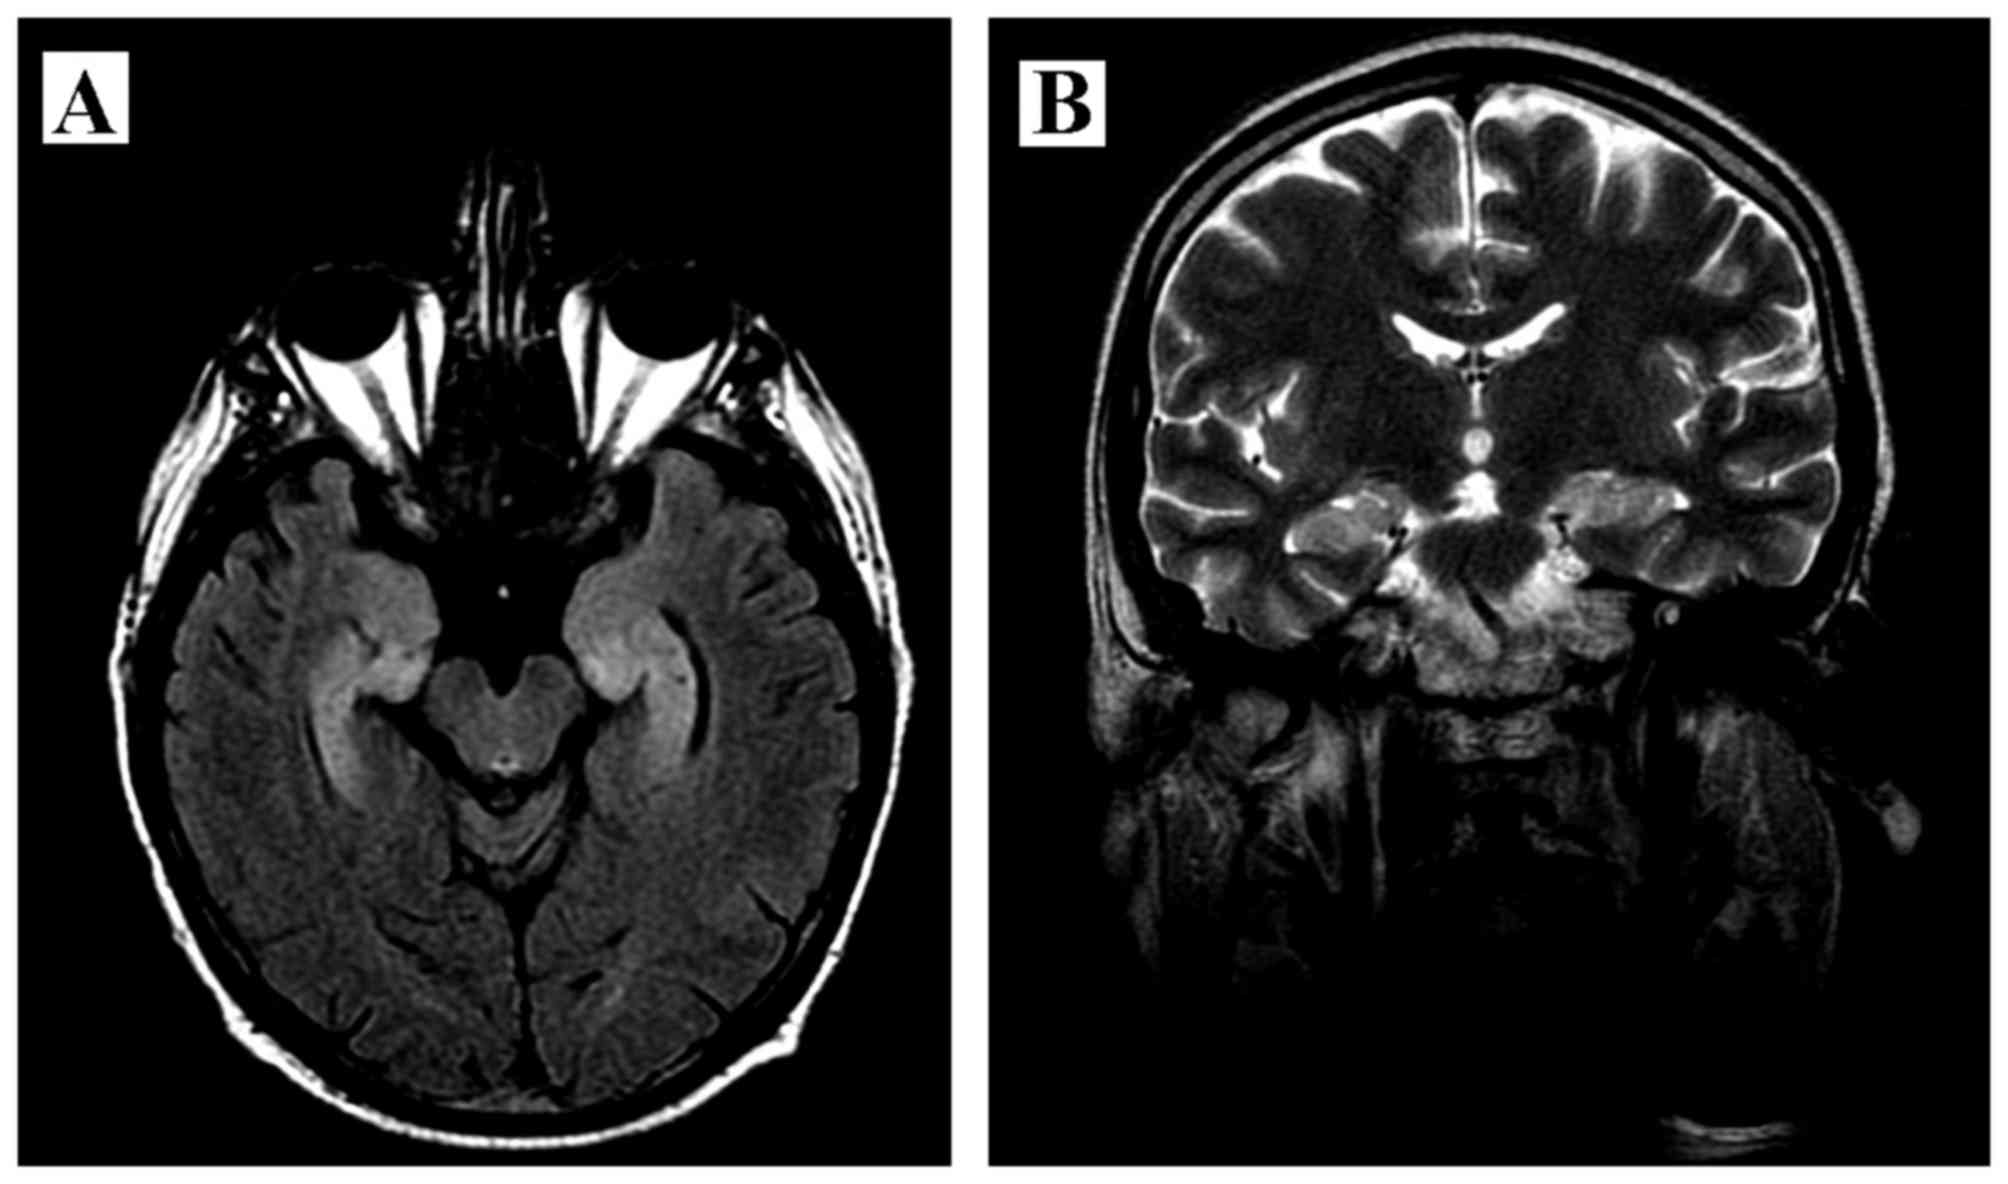

Paraneoplastic limbic encephalitis in a patient with extensive disease small‑cell lung cancer

Paraneoplastic limbic encephalitis (PLE) is a rare disorder infrequently accompanying malignancy, coexisting in ~50% of the cases with small‑cell lung cancer (SCLC). The pathomechanism of PLE is considered to be immune‑mediated, with production of specific anti‑Hu antibodies and activation of T‑cells directed against onconeural antigens present on both tumor cells and neurons. We herein report the case of a 50‑year‑old male patient who, prior to being diagnosed with SCLC, presented with typical symptoms of PLE (seizures, subacute cognitive dysfunction with severe memory impairment, anxiety and hallucinations). The initial brain magnetic resonance imaging examination revealed mild enlargement and hyperintensity of the hippocampal gyri bilaterally, with narrowed temporal horns of the lateral ventricles; the findings of the cerebrospinal fluid examination were compatible with the diagnosis of lymphocytic meningitis. Due to the suspected infectious origin of the disease, treatment with acyclovir and antibiotics was initially applied. However, following subsequent diagnosis of the underlying SCLC and the presence of antineuronal anti‑Hu antibodies in the patient's serum, the diagnosis of PLE accompanying extensive‑disease (ED) SCLC was confirmed. In addition to the standard cytotoxic therapy, throughout the course of his disease the patient also continued treatment with valproic acid (VPA) as prophylaxis for the initial seizures. VPA is known to be a potent histone deacetylase inhibitor that may reverse epigenetic changes in tumor cells and potentially improve the outcome of cancer patients. The patient succumbed to the disease 25 months after the diagnosis of malignancy; such a long course is observed in only ~5% of patients with ED SCLC. Therefore, it was hypothesized that the accompanying paraneoplasia and treatment with VPA may have improved the outcome in this patient.